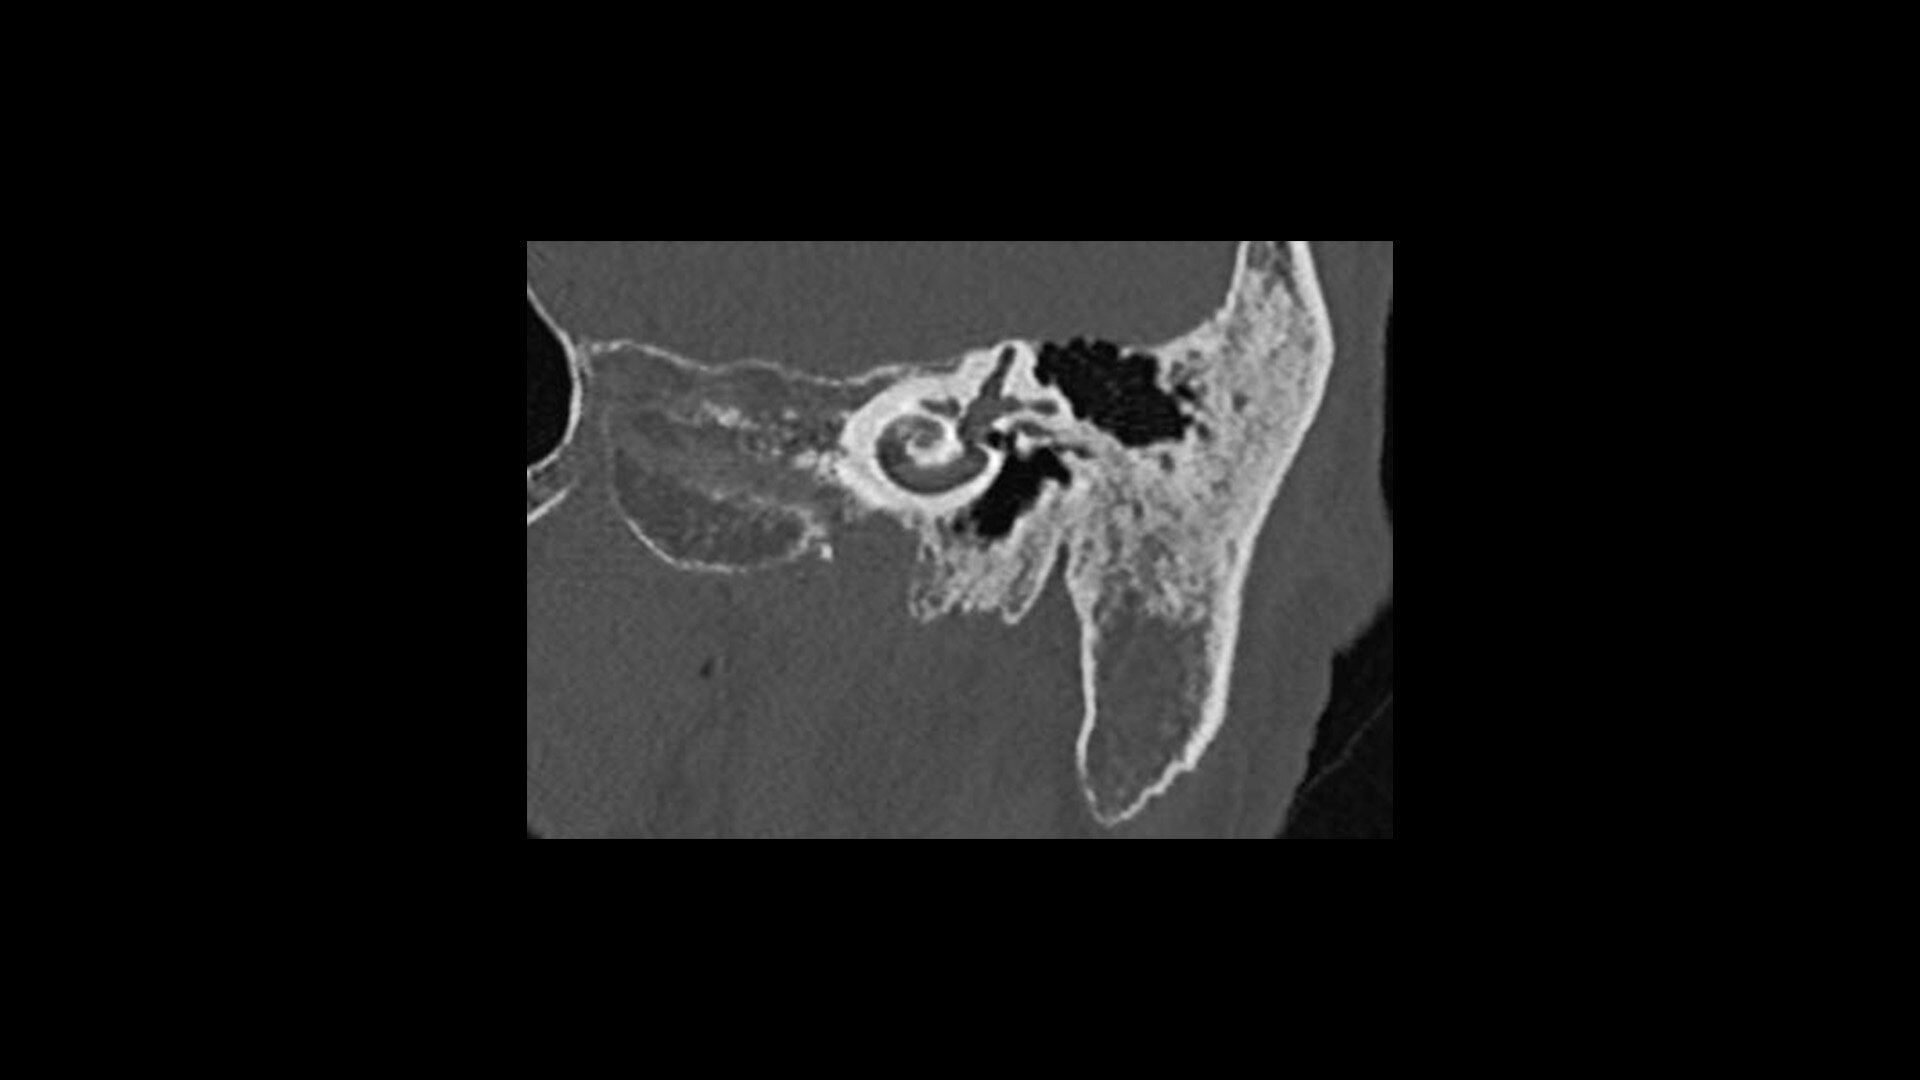

True Enhance DL

Designed to enhance what matters

True Enhance DL is a deep learning-based processing method intended for contrast enhancement of single energy images. True Enhance DL uses a dedicated Deep Neural Network (DNN) trained to estimate monochromatic, 50 keV GSI images from single-energy X-ray. This technology brings four deep learning models that the user can choose depending on different contrast enhancement phases by clinical tasks.